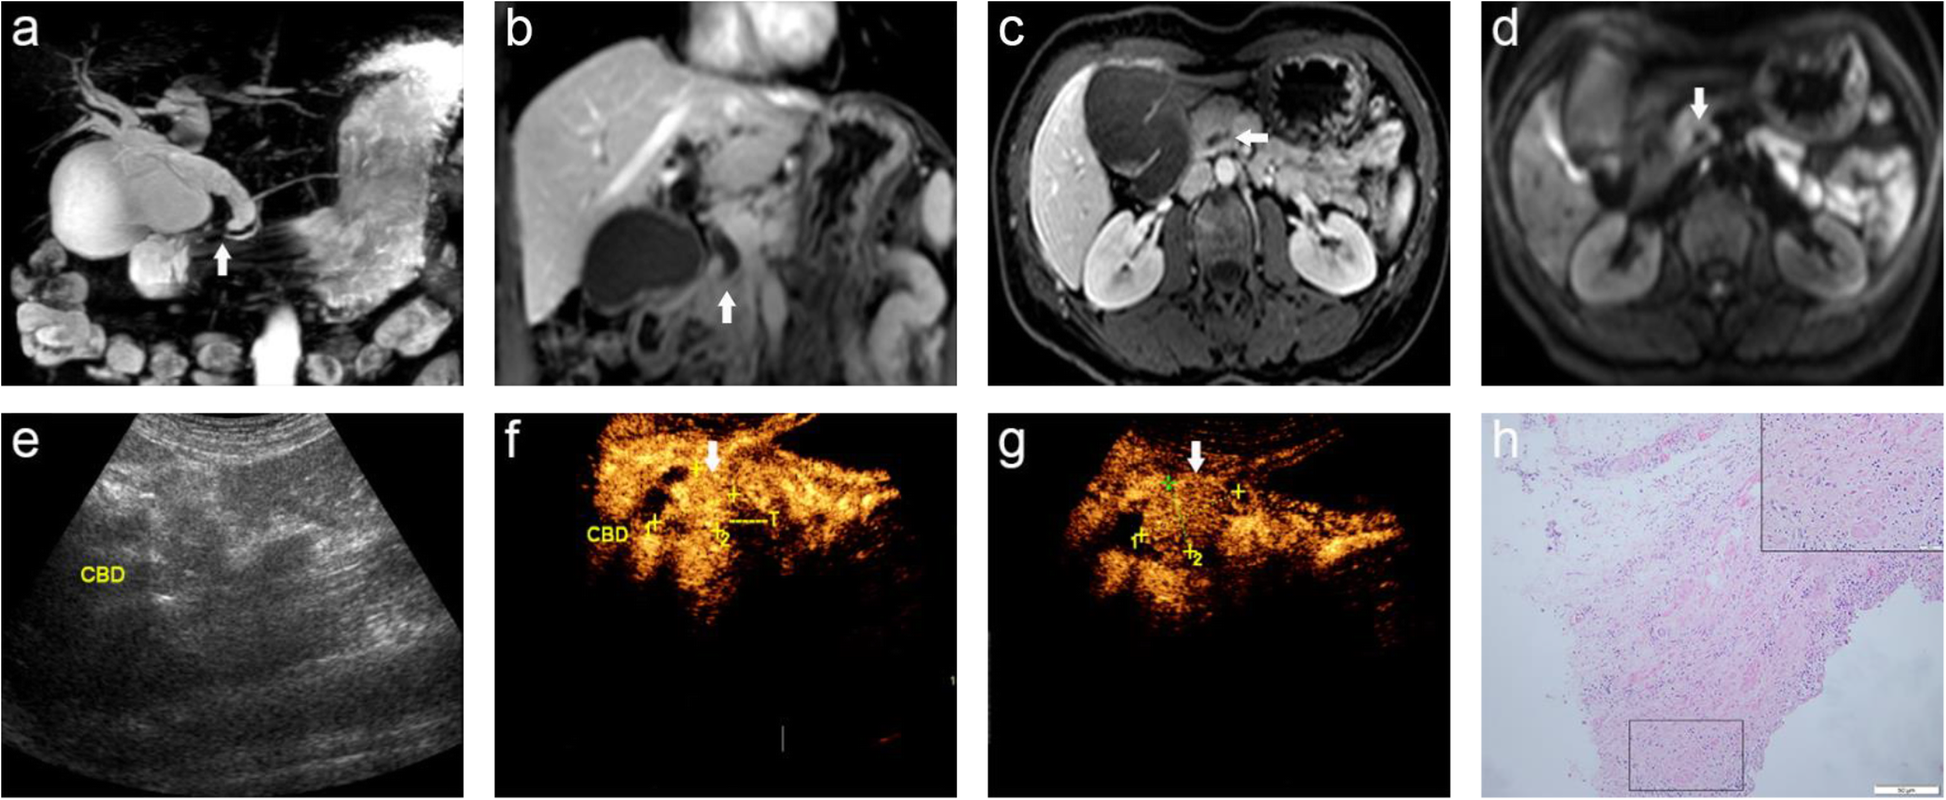

A 56-year-old female with common bile duct inflammation stenosis was misdiagnosed as having duodenal papillary carcinoma by CEUS; (a) MRCP image shows dilation of the intrahepatic and extrahepatic bile ducts with the lower part of the CBD tapering gradually (arrow) and the gallbladder increasing significantly. b Coronary contrast-enhanced T1WI shows the lower part of the CBD gradually becoming thin and occlusive (arrow) with no definite sign of mass-occupying lesions in the travel area of the intrahepatic and extrahepatic bile ducts; (c) Axial T1-weighted DCE-MR image shows the obstruction plane is in the lower part of the CBD (arrow), and the possibility of inflammatory stenosis and occlusion is considered. d DWI shows no abnormal signal is found; (e) CUS displays the choledochoectasia; (f, g) Uneven and highly intensified duodenal papilla region (arrow), and duodenal papillary carcinoma is considered; (h) Histopathological examination shows proliferative fibrous connective tissue of the bile duct wall, and the hyperplastic bile duct epithelium can be seen in the deep layer of the bile duct wall. CBD: common bile duct